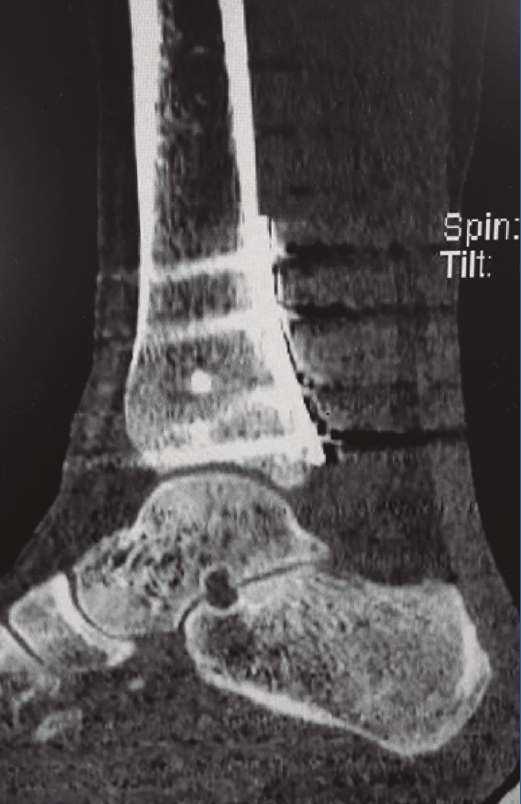

La clasificación de Bartoníček y Rammelt(14)(Tabla 2), publicada en 2015, está basada en 141 casos consecutivos de fracturas de tipo Weber B o C con fractura de MP analizadas por TC en planos transverso, horizontal y frontal, y reconstrucción 3D. Las fracturas fueron clasificadas en 5 tipos, con especial referencia a la afectación de la incisura fibular de la tibia: el tipo 1, fragmento extraincisural, es una fractura extraarticular; el tipo 2, fragmento posterolateral, es la más frecuente; el 3, fragmento posteromedial en 2 partes (Figura 2); el 4, gran fragmento triangular posterolateral, donde puede apreciarse el signo de doble contorno; y el tipo 5, una fractura irregular osteoporótica, que no puede encuadrarse en ninguno de los tipos anteriores.

Figura 2. Imagen de tomografía computarizada de una fractura de tipo 3 de Bartoníček y de tipo II de Haraguchi.